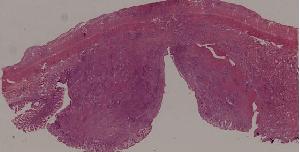

92. Typhoid fever of intestine